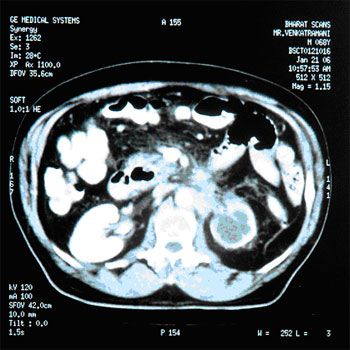

CA.Pancreas :

INITIAL STAGE

15-Aug-2005

AFTER HERBAL ONCOLOGY

21-Jan-2006